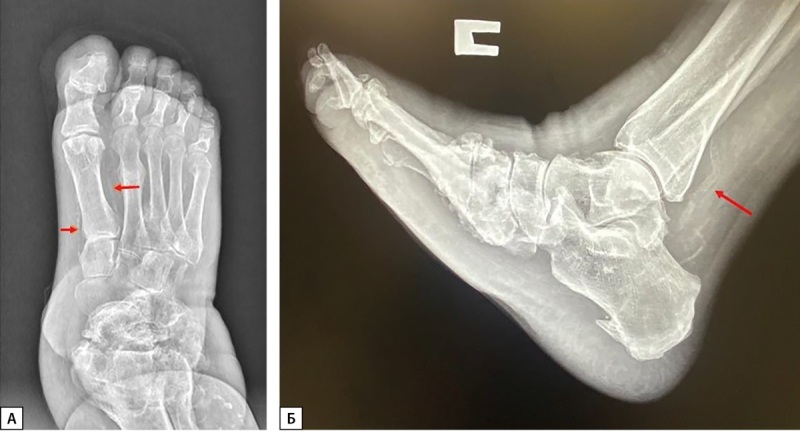

Diabetic neuropathy is one of the most common diabetes mellitus complications associated with mediocalcinosis of the lower extremities, a significant decrease in feet bone mineral density, and a high incidence of cardiovascular disease. In most cases, calcium-phosphorus metabolism changes occur in patients with diabetic neuroarthropathy, or Charcot foot, when we can observe feet local osteoporosis, which in 90% of cases associated with a vessel's calcification of the lower extremities in the majority of diabetes population. A large number of studies presented literature have demonstrated that patients with Charcot foot can have accelerated bone metabolism and increased bone resorption. Patients with Charcot foot often have crucial abnormalities in the calcium-phosphorus parameters, bone metabolism, and levels of vitamin D and its metabolites. In addition, the duration of diabetes mellitus, the degree of its compensation widely affects the development of its micro- and macrovascular complications, which could also accelerate the development of mineral and bone disorders in these types of patients. Multifactorial pathogenesis of these disorders complicates the management of patients with a long and complicated course of diabetes mellitus. This review discusses the peculiarities of vitamin D metabolism, the importance of timely diagnosis in phosphorus-calcium disorders, and the specifics of therapy in these patients. Special attention is paid to the timely diagnosis of the Charcot's foots acute stage based on the bone marrow edema by MRI evaluation and the possibility of reducing the immobilization period.